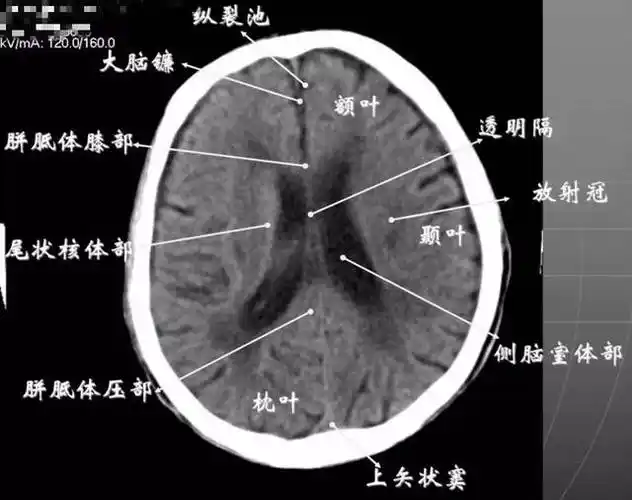

基底节区解剖位置关系图ppt模板

基底核与基底节区解剖与定位

基底节区:概念不清. 可能包括:基底节,黑质,红核,及其周围白质区域.